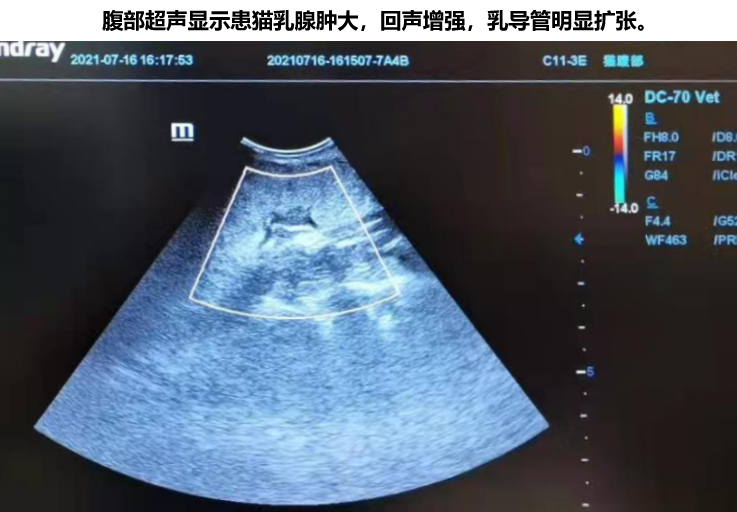

临床检查显示患猫精神良好,皮肤较烫,体温39.4℃,BCS:5,左侧乳腺肿大发热,乳腺破溃初始面积为4cmX5cm。后续的血液检查和超声检查的结果确诊为乳腺炎。